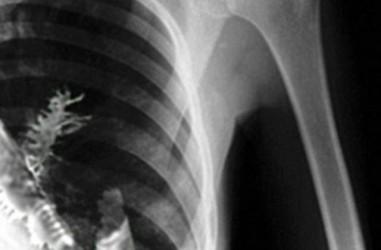

Ron Svedan tinha 75 anos quando começou a sentir dores e falta de energia. Após alguns exames, ele pensou que tinha um tumor no pulmão, mas ele estava longe de estar certo. O Raio-X mostrou que ele tinha algo em seu pulmão, embora tivesse que esperar por testes para descobrir se era câncer ou não. Para surpresa de todos, os médicos acharam uma planta de ervilha crescendo no local. Como isso aconteceu? Ron deve ter inalado acidentalmente a semente da planta e por ser uma atmosfera calorosa a planta encontrou o local perfeito para crescer. Ela finalmente foi removida após uma cirurgia e o homem voltou ao normal